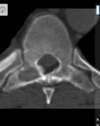

Osteoma Osteóide - A TC mostra o nidus radioluscente, cercado por reação esclerótica e , as vezes, pode mostrar um ponto esclerótico dentro do nidus.

Predomina 10 - 30 anos.

Nicho radiotransparente < 1cm circundado por reação esclerótica. Localização cortical / justacortical em ossos longos: femur proximal e tibia.

Clinica tipica: dor mais intensa a noite aliviada por AAS.

Quando nidus > 2cm = osteoblastoma. TC é a modalidade de escolha (RM pode não ver o nidus).